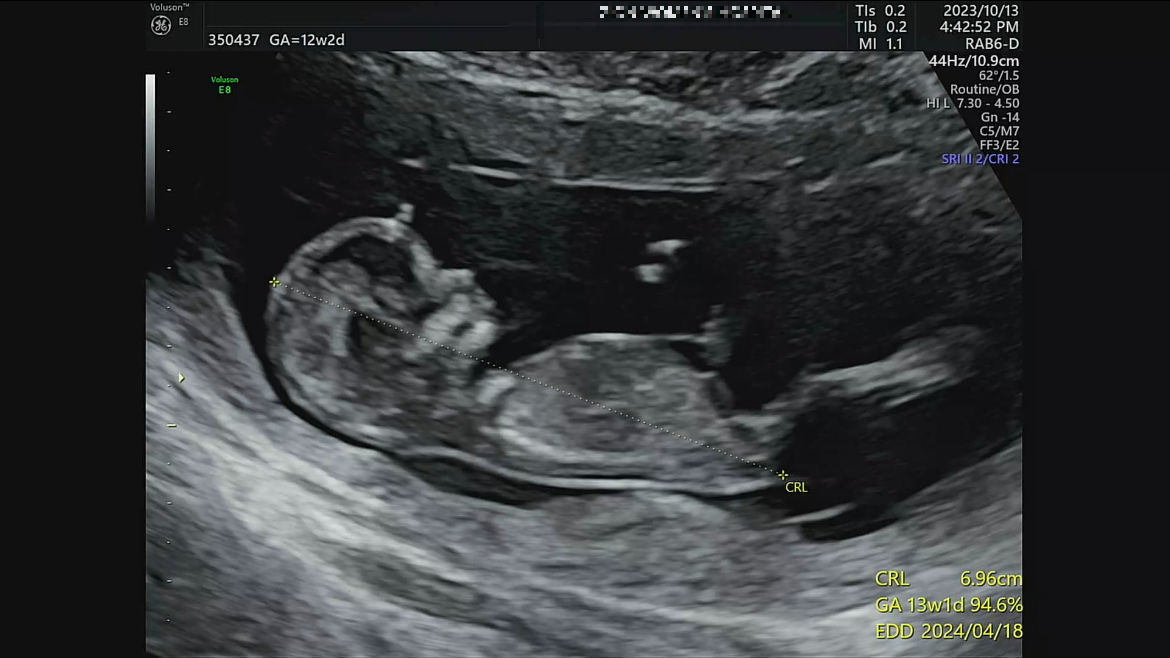

4. 12주 각도법(장꾸맘의 각도법) 성별 확인 방법: 12주 이후 (딸 = 맞춤)

네*버 유명 맘카페에서 각도법을 잘 봐주기로 유명하신 장꾸맘님이 계십니다. 저는 12주차 진료 후에 바로 동영상과 사진을 업로드해서 장꾸맘님에게 문의를 드려보았답니다. 지금은 따로 카페를 운영하셔서 아래 첨부해 드릴 카페로 가입해서 문의해 보시면 됩니다.

태아 초음파에서 옆모습의 척추와 성기의 각도를 통해 볼 수 있는 방법을 12주 각도법이라고 부릅니다. 12주보다 좀 더 이르면 애매할 수도 있고, 12주가 지나면 성기의 형태로도 추정할 수 있기 때문에 가장 빠르게 성별을 확인할 수 있는 방법입니다. 툭 튀어나온 부위가 척추와 평행을 이루고 있다면 딸, 30도정도의 각도를 이루고 있다면 아들이라고 합니다. 16주 이상 됬을 때 정확한 성별을 판단하기 이전에 가장 정확하게 확인 할 수 있는 방법입니다.

장꾸맘님의 주변 적중률은 100%였고, 인터넷상으로 돌아다니는 적중률도 99%는 되는듯합니다. 일단, 확실할 경우에는 딸에 한표요! 아들에 한표요! 라고 말씀해 주시고, 정말 안보이시는 동영상의 경우 업로드 재요청을 해주시거나, 조건부로 잘 보이지 않는 동영상이지만, 혹은 조심스럽게, ~에 한표요 라고 얘기해 주신답니다. 저의 경우에는 12주2일차 동영상을 올렸고 단답으로 딸에 한표요! 라고 답변해 주셨답니다.